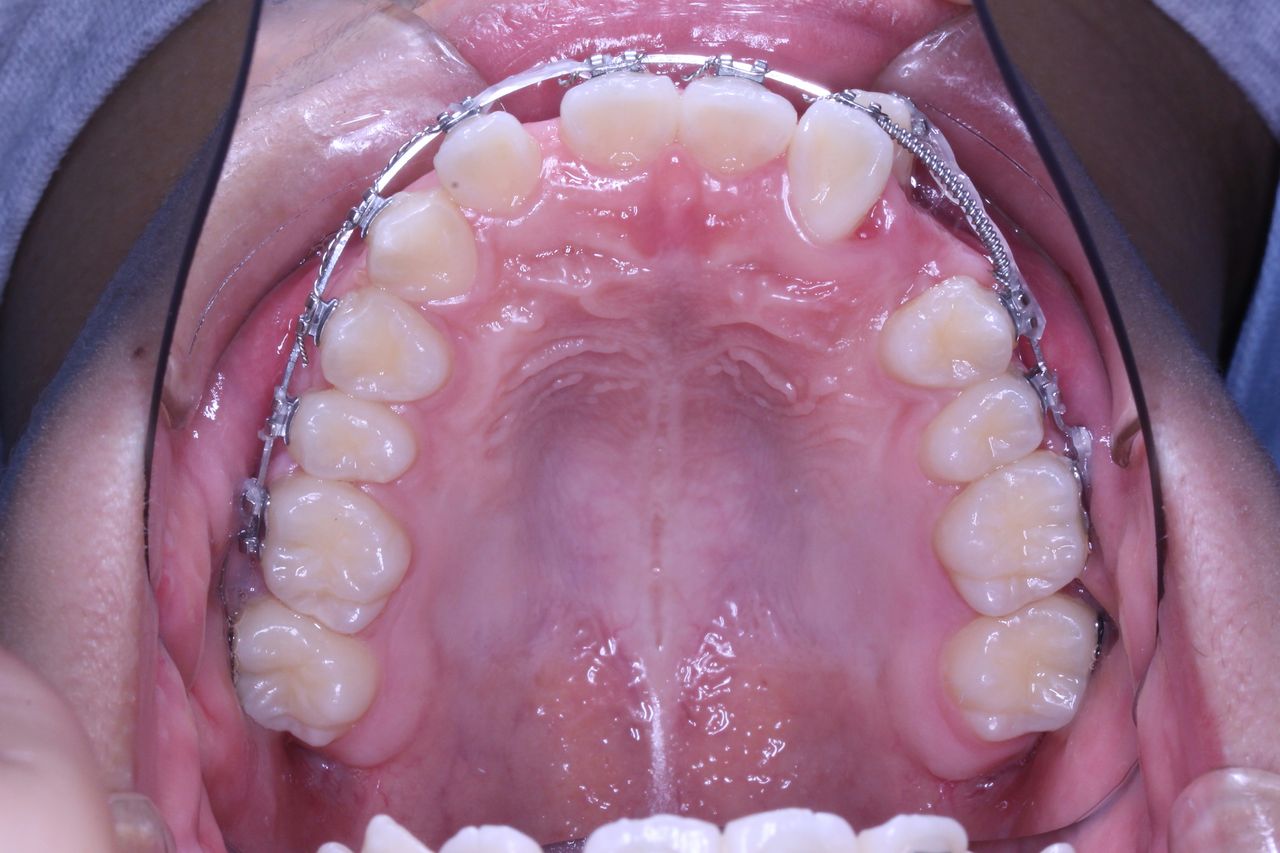

上からみてみるとどうでしょうか?

もう少し犬歯が後方に移動してもらえると、2番目の歯が前方に移動可能な感じです